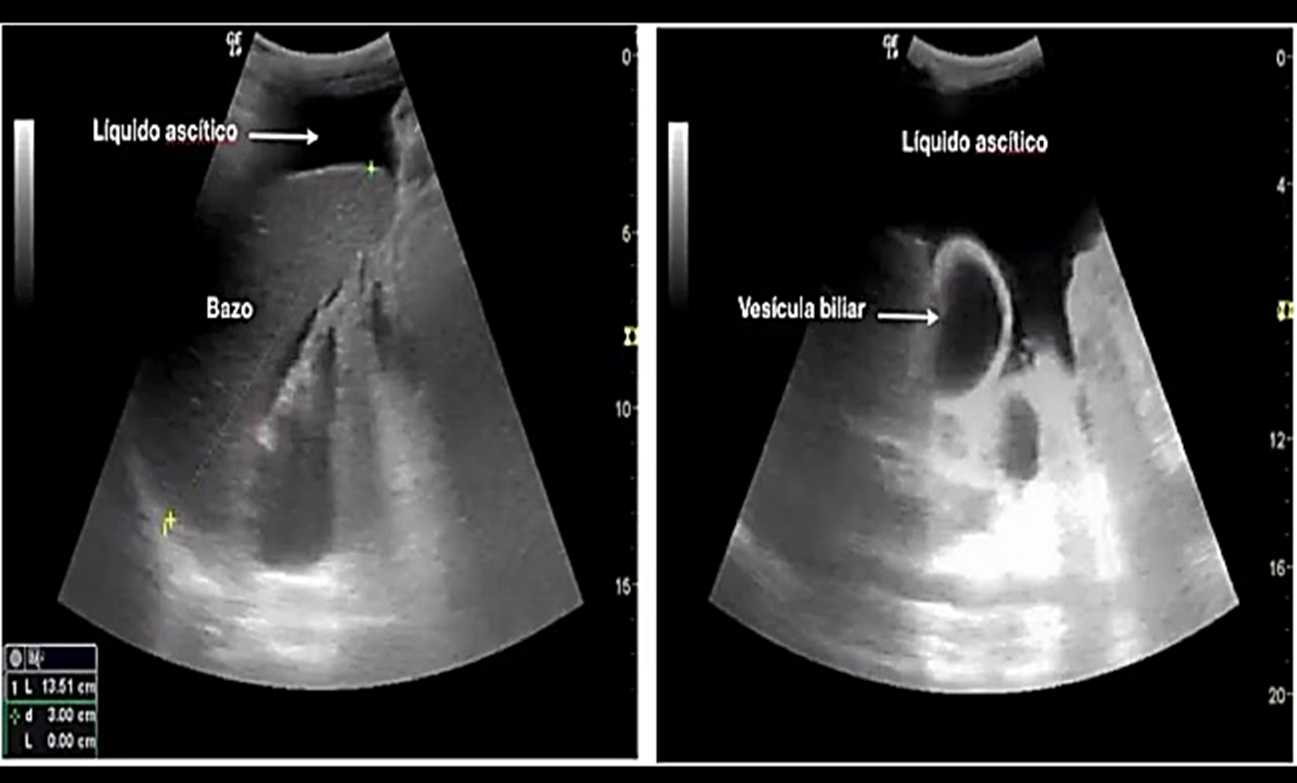

• Abdomen agudo quirúrgico por biliperitoneo secundario a colecistectomía laparoscópica segura

Milena Prada, Jorge Bittar, Hugo Reyes, Luis Traviezo-Valles

e1228

• PDF